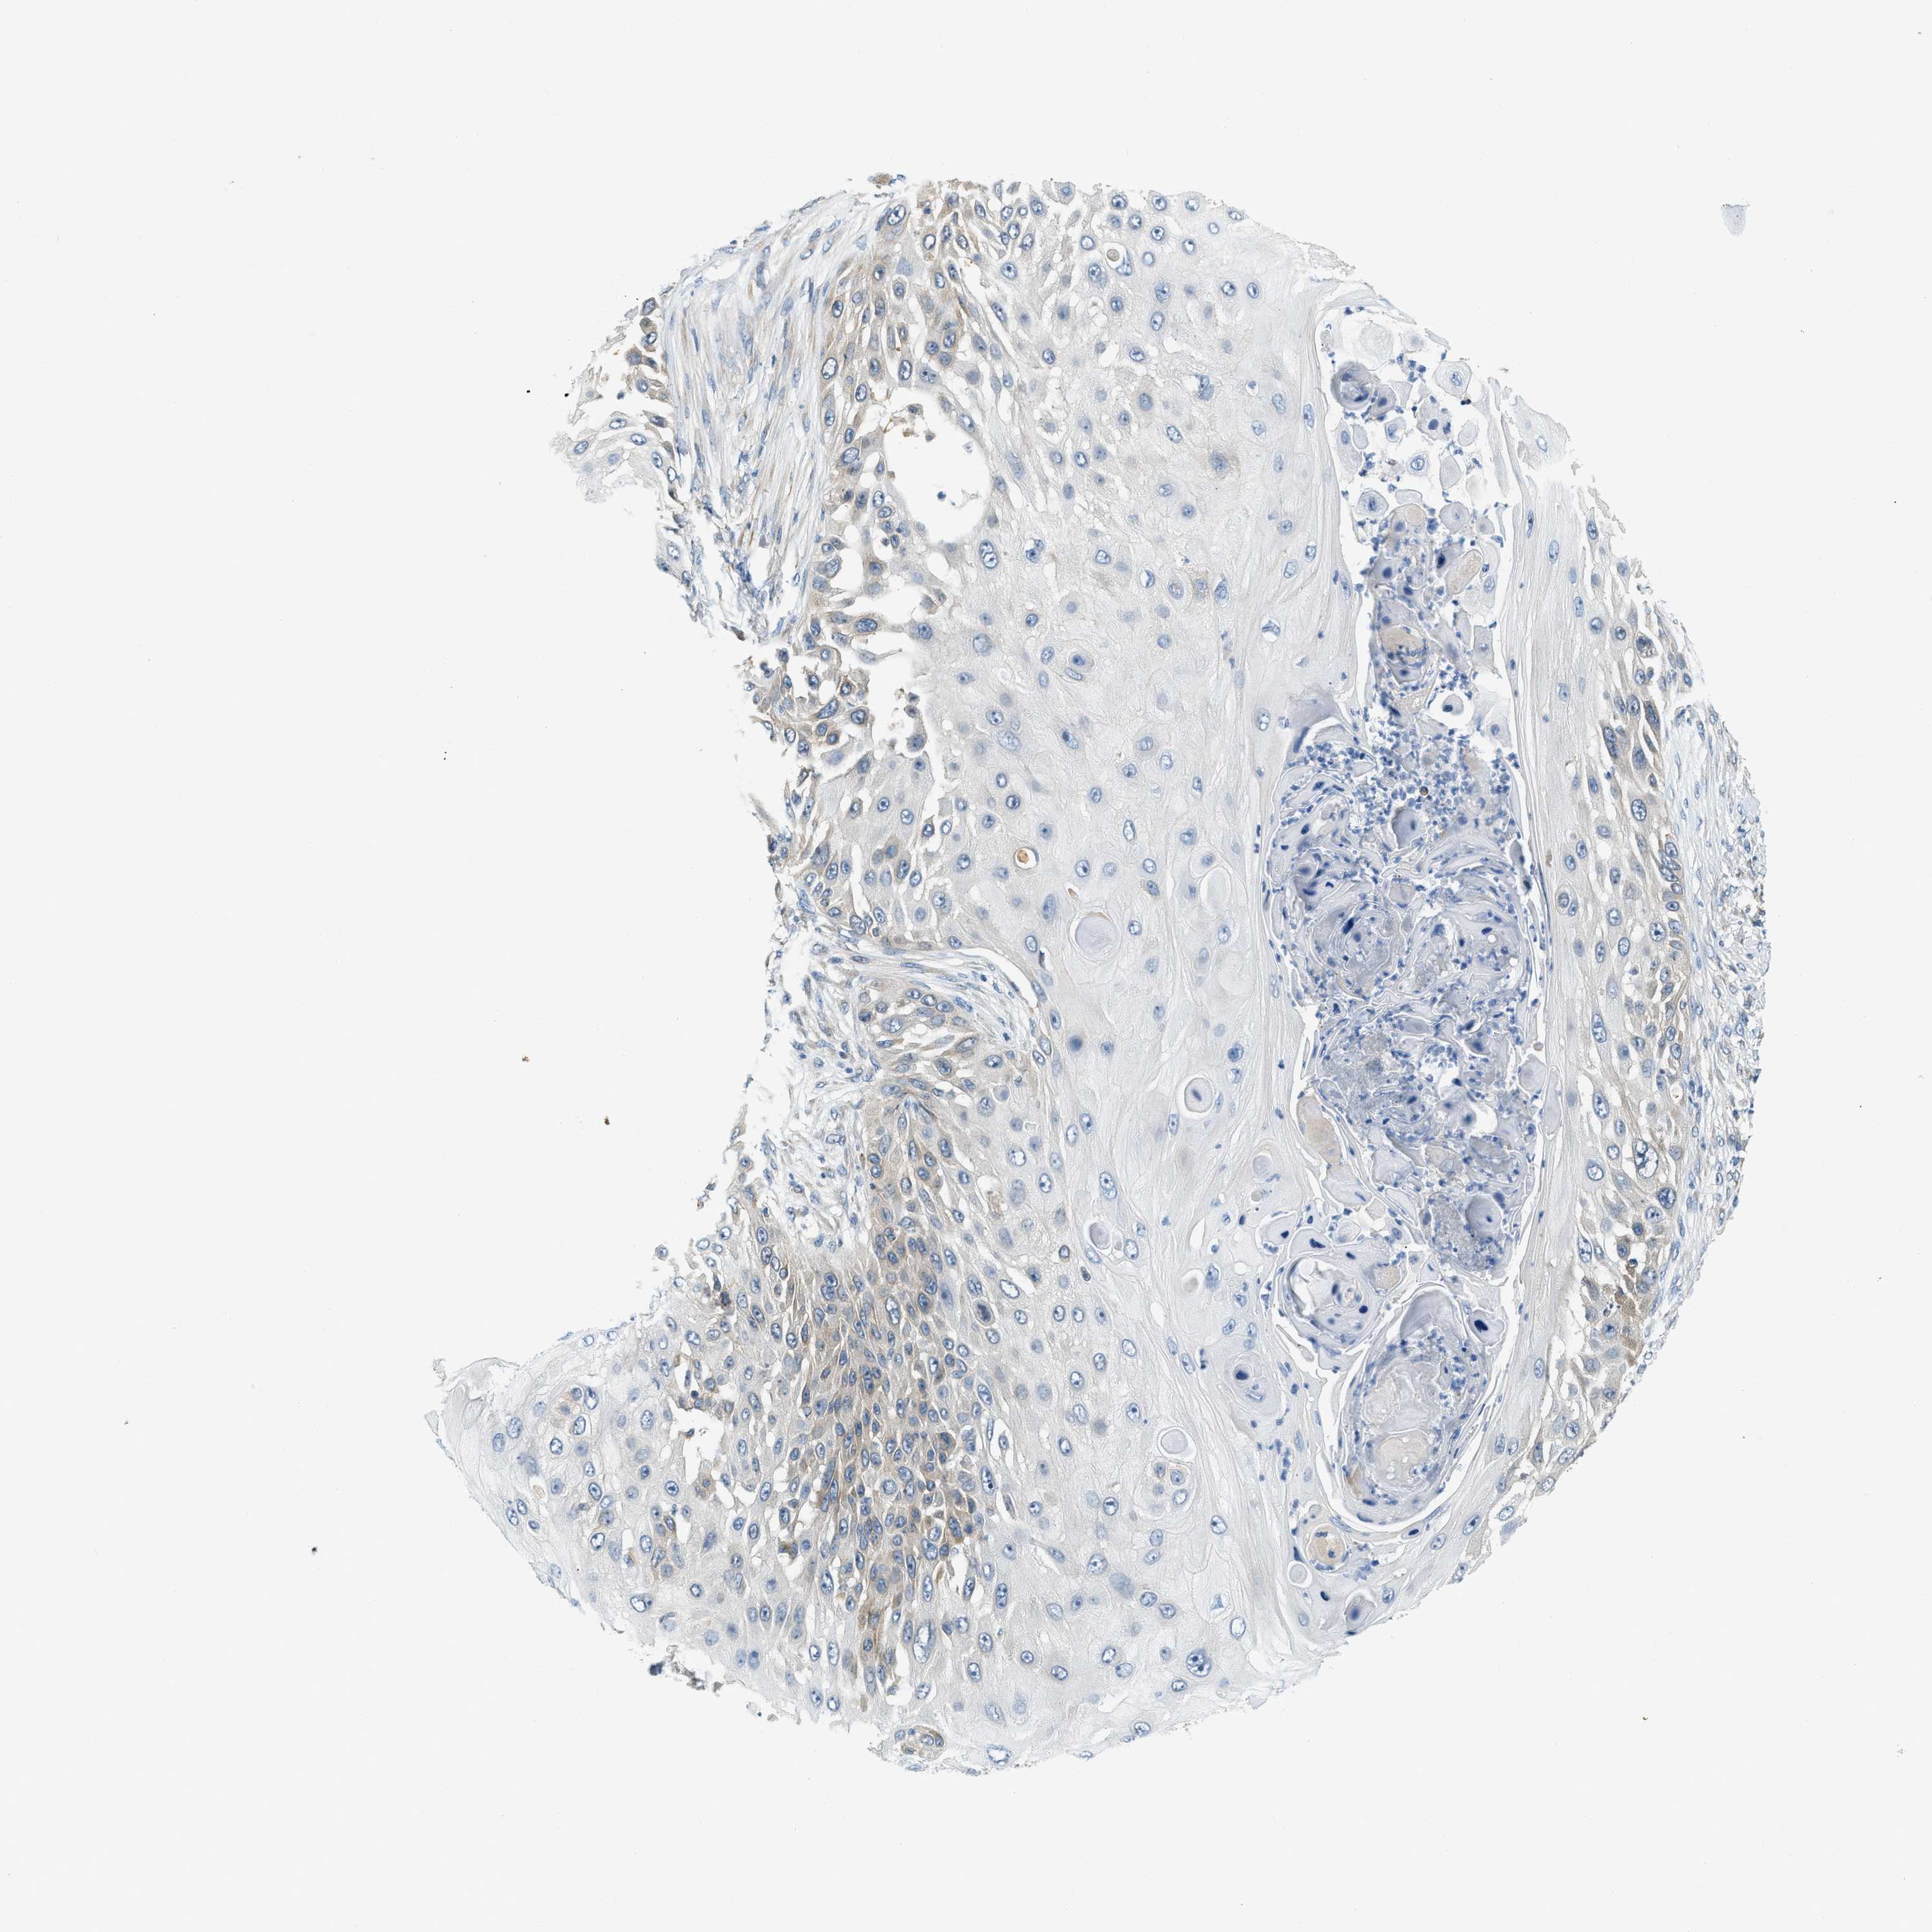

Basal cell and squamous cell cancer

SKIN CANCER - Protein expressioni

A mouse-over function shows sample information and annotation data. Click on an image to view it in a full screen mode. Samples can be filtered based on level of antibody staining by selecting one or several of the following categories: high, medium, low and not detected. The assay and annotation is described here.

Each image is clickable and will lead to virtual microscopy that enables deeper exploration of all samples and also displays staining intensity scores, fraction scores and subcellular localization as well as patient and tissue information for each sample.

Antibody HPA019259

Basal cell carcinoma